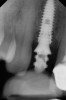

Fig 2. Radiograph showing implant was placed too deep and the diameter of the implant may be slightly larger than what was needed.

Figure 2

Caneva et al also suggested placing implants in a lingual (eg, cingulum) position to achieve optimal esthetic outcomes. The authors assessed the effect of implant positioning on resorptive patterns of the alveolar bone crest and demonstrated the importance of placing implants in a lingual position to minimize buccal bone resorption and thus prevent exposure of the implant. In their study, an average of 0.6 mm more buccal bone resorption was seen on implants that were placed in the center of the socket when healing after 4 months was compared histologically with implants that were positioned toward the lingual bony wall.17 In addition, placing a wider-diameter cylindrical implant in the extraction socket with the aim of filling the void between the implant and the inner socket wall was also shown to present greater buccal alveolar bone resorption (Figure 2).18,19 Based on these findings, it has been suggested that implant placement be performed in the palatal position of the socket to allow the formation of a gap between the implant surface and the inner buccal bone wall surface.19 More recently, in a retrospective cohort study, Cosyn and coworkers evaluated 115 patients who underwent implant placement with function. At 31 months, the buccal shoulder position of the implant was significantly associated with an increased likelihood of midfacial recession.3